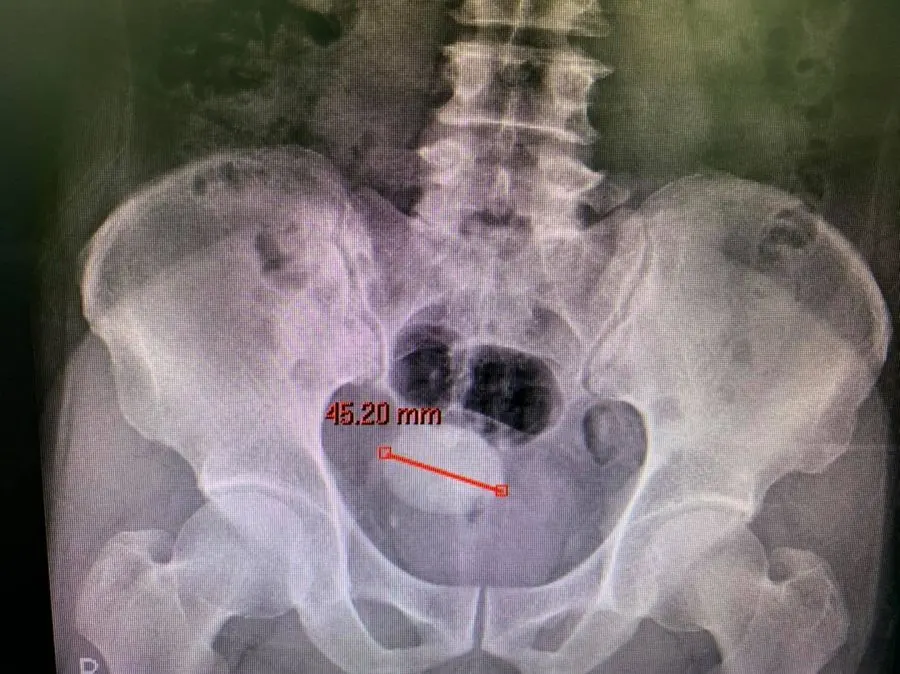

ภาพที่เห็นคือ "นิ่ว" ไม่ใช่เจียวกากหมู